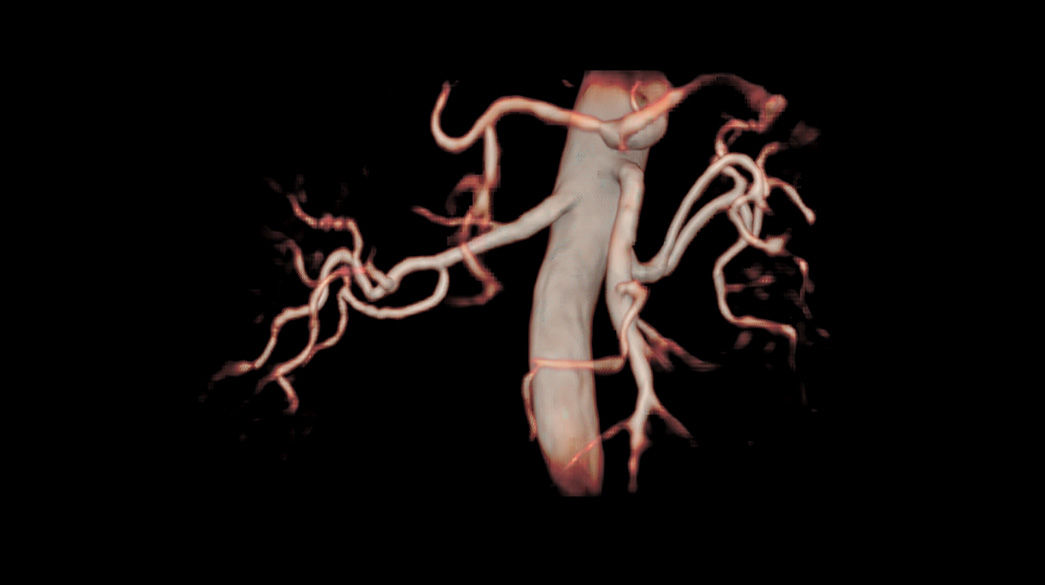

Fluoroscopic triggering is a real-time bolus detection method of contrast arrival for vascular scans.

TRICKS

MR Angiography imaging that helps accelerate the temporal domain of 3D dynamic imaging – without compromising spatial resolution.

Inhance Suite

Improves workflow with easy setup through visualization of blood flow in diverse anatomies. Includes: 3D IFIR, 3D Velocity, 2D InFlow, 3D DeltaFlow